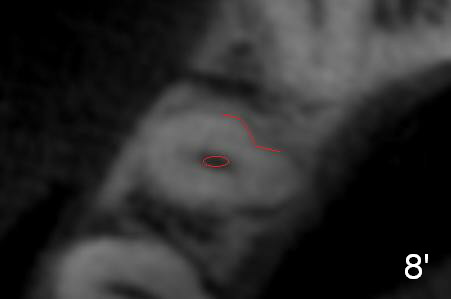

In fact CBCT has ben taken for #14 RCT and is reviewed prior to this case. If CT were reviewed, finding the extra canal would be easier (Fig.6 coronal section). It appears that the apical canals are blocked (Fig.7). The canal is split at the middle of the root, as shown in Fig.8,8' (axial upper section, as shown by the upper dashed line in Fig.6) and in Fig.9,9' (axial lower section, as shown by the lower dashed line in Fig.6). The buccal canal should not have been debrided with 40/.04 rotary file (30/.04 would have been better). In all, the tooth has two fused roots (Fig.3,9,9').